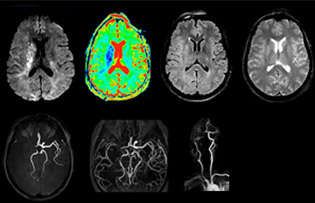

“In France, stroke is usually imaged with MRI, not CT, even for emergency treatment. This is because MRI helps us directly visualize ischemia in the acute phase, but can also help rule out differentials such as MS and hematoma. In addition, we can assess the intracranial and extracranial vessels during the same examination,” says Dr. Savatovsky.

The first challenge in MRI of stroke is speed. The patient typically arrives from an ambulance in the MRI preparation room and the installation is done on a separate dock outside the scanner room. “The venous access is placed during the neurological examination. If the delay from the first symptoms allows the patient to receive thrombolysis we do a very fast examination that typically lasts about 11 minutes including the pre-scans. In the case of transient ischemic stroke we usually add ASL perfusion because in some symptoms with negative diffusion, ASL sometimes indicates a vascular origin.”

“Ingenia provides great flexibility in the parameters setting. We can tune a sequence the way we want,” says Dr. Savatovsky. “For example, in a stroke exam we use a FLAIR sequence of about two minutes instead of the four-minute FLAIR we use for MS. The diffusion is 30 seconds, the T2*-weighted scan is 30 seconds, the angiography scan time is less than one minute. Ingenia is a great scanner in that situation; even with these fast sequences we can achieve good images with good SNR. When the first sequence tells us that it’s not an ischemic stroke but a hemorrhagic stroke, we may switch to a time-resolved angiography to look for vascular malformations and venous thrombosis.

The ideal stroke protocol?

“Every center is different, but for me the ideal protocol for stroke includes diffusion weighted imaging, FLAIR, and fast susceptibility imaging,” says Dr. Savatovsky. “Our fast susceptibility weighted imaging takes 50 seconds, so it’s as fast as T2*-weighted imaging. It visualizes hemorrhage but also the clots. We also do 3D MR angiography that provides information on cervical and brain vessels. If the patient does not need immediate treatment, or if additional information is needed to decide on treatment, we might also add perfusion imaging and post-contrast T1-weighted imaging.”